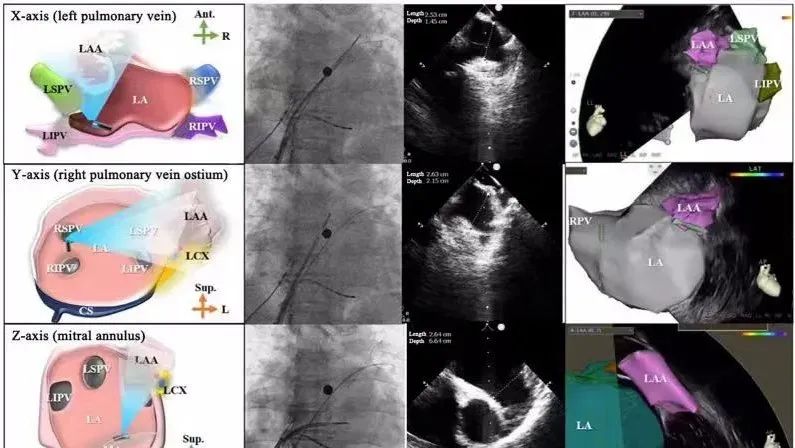

一種與心導管檢查相結合的超聲心動圖診斷新興技術,通過將超聲探頭置于心腔內部,發射并接收超聲信號,來精確獲取心臟解剖結構、心臟血流動力學等信息的實時成像。與其他影像技術相比,ICE技術具有操作簡單、無輻射、安全性高、手術效率高、實用等優勢,ICE在很大程度上有望取代經食道超聲心動圖(TEE),成為電生理和結構性心臟病領域的理想成像方式。

心腔內超聲(ICE)技術壁壘極高,國內主要廠商核心部件仍舊為進口,集成了超聲和圖像處理最前端技術,包括超聲探頭、線纜、軟件成像算法等,是當前內窺超聲方向最具挑戰的領域。ICE的應用經歷了2D平面成像、3D三維立體成像、以及4D的實時三維立體成像階段。